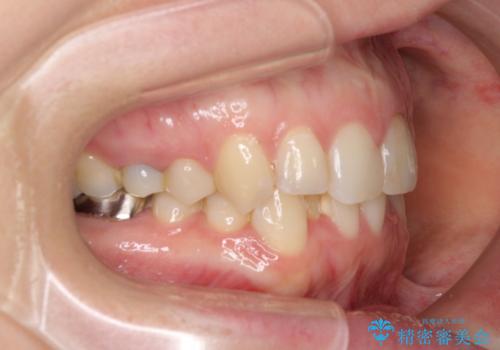

主に下顎歯列全体の後方移動とIPR(歯と歯の間を削る)によってデコボコが解消するように設計し、インビザラインにより治療を行うこととしました。

矯正治療後半に下顎左右奥歯をセラミッククラウンにて補綴し、その後インビザラインによる歯列の仕上げを行うこととしました。

下顎前歯の叢生が速やかに改善されたため、1年3か月で治療を終えることができました。